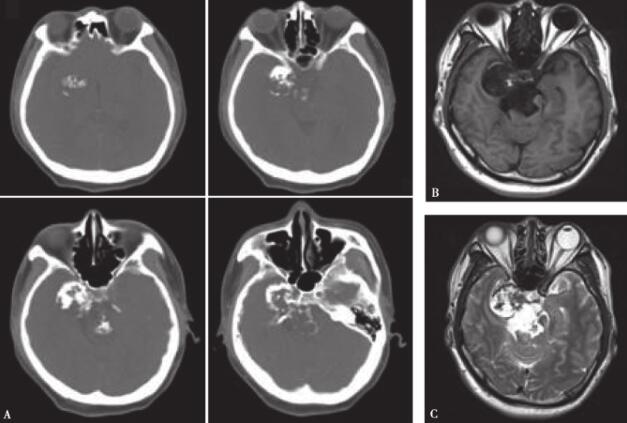

头颅CT及MRI示右侧中后颅窝占位性病变。头颅CT骨窗(图1A)显示病灶内多发不规则钙化,内侧压迫鞍旁骨质致其变薄。MRI T1(图1B)低信号,T2(图1C)高信号。术前拟诊骨源性肿瘤(偏良性)可能。

图1术前影像学检查

A. CT可见明显钙化;B. T1低信号;C. T2高信号

从影像学表现上看,本例患者术前骨窗位CT提示肿瘤呈压迫性生长,而不是侵袭性生长,所以影像学支持肿瘤为高分化或者偏良性病变可能。

颅底近中线骨源性肿瘤常见软骨黏液样纤维瘤、软骨肉瘤和脊索瘤等,最需要鉴别的是脊索瘤和软骨肉瘤,因为二者预后不同。文献报告脊索瘤更多见表现为以斜坡为中心生长,DWI弥散受限更多,增强后不强化或不均匀强化。软骨肉瘤多偏于一侧,呈不均匀强化或实质性强化。分化差时,T2信号减低。本例影像学:病灶占据中、后颅窝偏侧,CT提示肿瘤呈压迫性生长为主,而不是骨质破坏,MRI T2呈高信号。综合影像学表现,考虑软骨黏液样纤维瘤或高分化的软骨肉瘤可能大。最终病理亦证实为高分化软骨肉瘤。